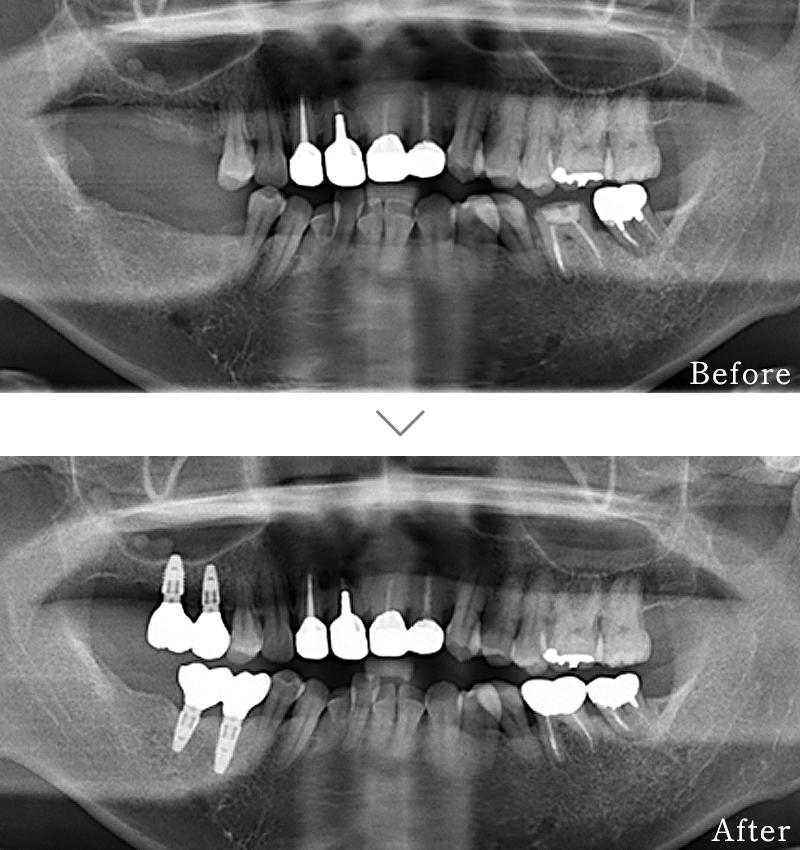

CASE2

主訴 奥歯でしっかりと噛むことができない、入れ歯もすぐに壊れてしまうとのことで来院されました。

治療法 下の奥歯を右1本、左2本のインプラントとセラミックの被せ物で噛み合わせを回復しています。

治療期間 4ヶ月

費用 CT:16,500円(税込)

+ インプラント治療:1,577,400円(税込)

合計:1,593,900円(税込)

副作用

• 歯周病に感染・発症し重度に進行するとインプラントが抜けてしまうことがあります。

• 手術後は数日間腫れが出る場合があります。